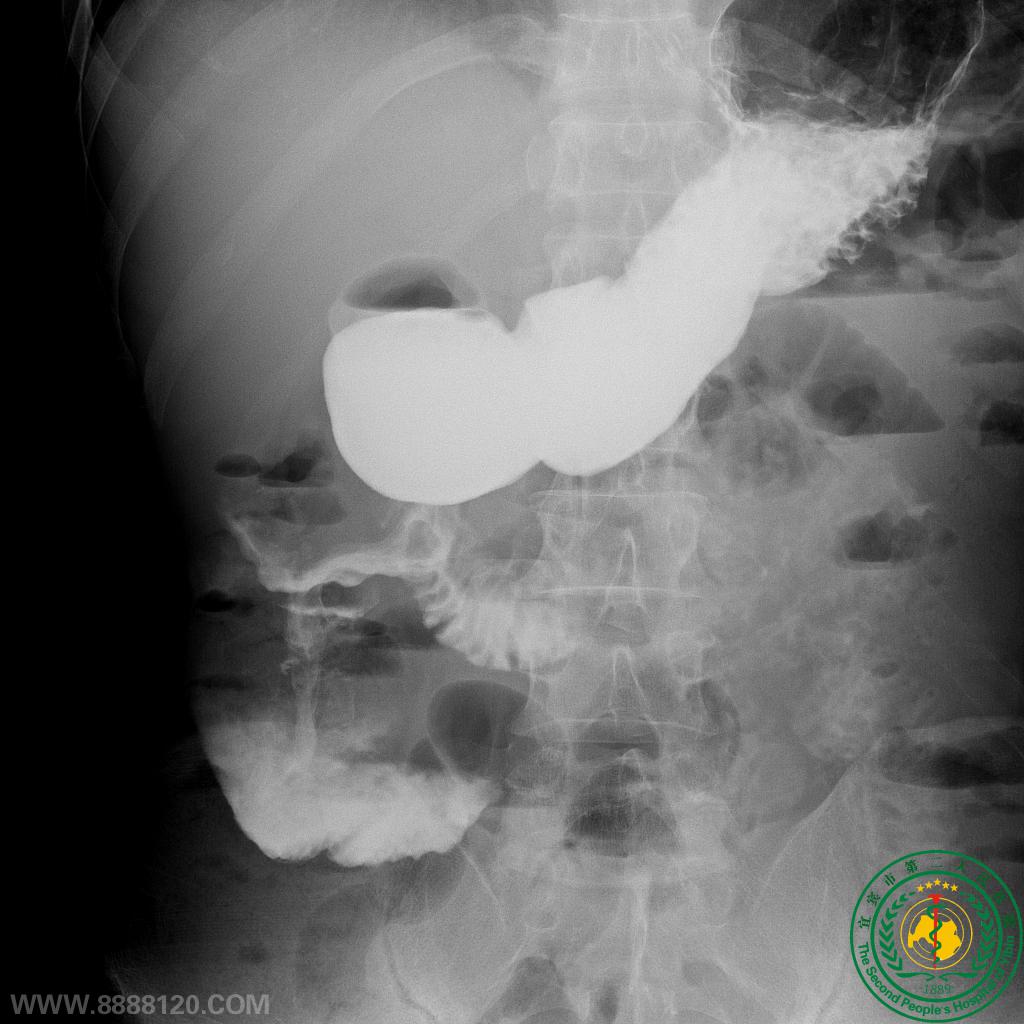

胃肠外科联合肝胆外科再次成功实施一例联合胰十二指肠切除的扩大右半结肠癌根治术

胃肠外科联合肝胆外科再次成功实施一例联合胰十二指肠切除的扩大右半结肠癌根治术26956